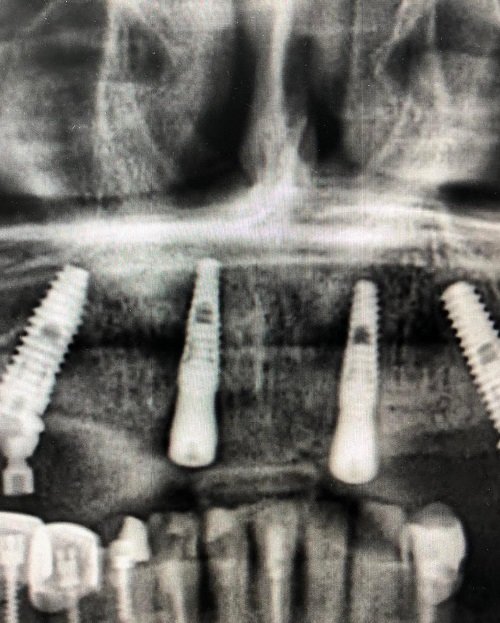

«Все на 4-х имплантатах»

«Все на 4-х имплантатах» - данную методику мы применяем нашим пациентам с полным отсутствием зубов.

Именно эта методика позволяет позволяет в кратчайшие сроки, около 3-5 дней зажить полноценной жизнью.